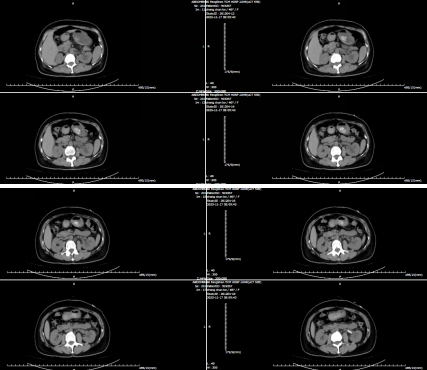

肾盂输尿管连接部狭窄,通俗来说就是肾脏和输尿管连接的地方变窄了,尿液排不出去,会憋大肾脏(肾积水),损伤肾功能。手术治疗的核心就是“剪掉窄的部分,把好的肾盂和输尿管重新接好”,让尿液能顺畅流走。此种术式称为“肾盂输尿管成形术”,是泌尿外科中技术成熟、疗效确切的手术,但因治疗的疾病发病率不高,且对设备和医生技术有一定要求,整体不算普及性手术。泌尿外科早已常规开展此项手术,积累了丰富经验,为进一步保障手术安全与效果,针对复杂病例(如合并重度肾积水、多次术后复发等情况),北京大学人民医院泌尿外科熊六林主任医师联合评估——术前和专家共同梳理患者病情、优化手术方案,术中若遇到特殊情况也会及时沟通协作,术后则结合专家建议完善护理细节,每一步都会反复核对、严格把控,始终把 “安全解除梗阻、最大程度保护肾功能” 放在第一位。术前CT如下图: